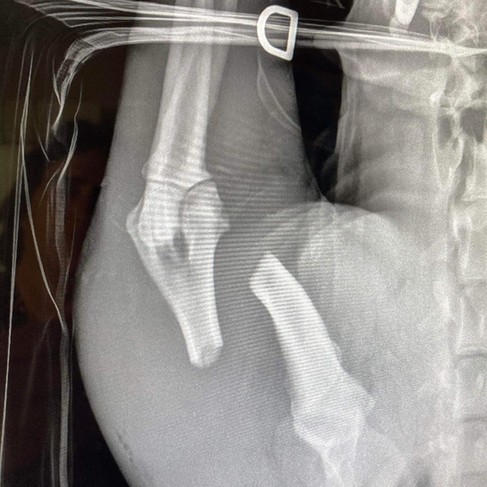

Two months ago, Sophie, a 5-6 month-old German Shepherd, was turned in to the shelter by her owner because she couldn’t afford medical care. The owner said Sophie was attacked by another dog two days prior. She clearly had a broken front leg and over 50 puncture wounds. She was covered in dirt so the first thing done by our staff member Chelsea was bathe her. Despite the pain she must have been feeling, Sophie was so sweet and loving to everyone. Our kennel supervisor Jen took her to an off-site vet, Dr. Boyd, for X-rays and exam. He cleaned up her wounds and put her on pain meds and antibiotics. He said the infection was already setting in so she was probably attacked at least a week before being turned in.

Our Rescue Liason, Susanne, reached out to Coastal German Shepherd Rescue OC (https://www.facebook.com/coastalgsr). They agreed to come get her the next day. They took her to their vet. She underwent surgery to repair her broken leg, along with the insertion of multiple drains.